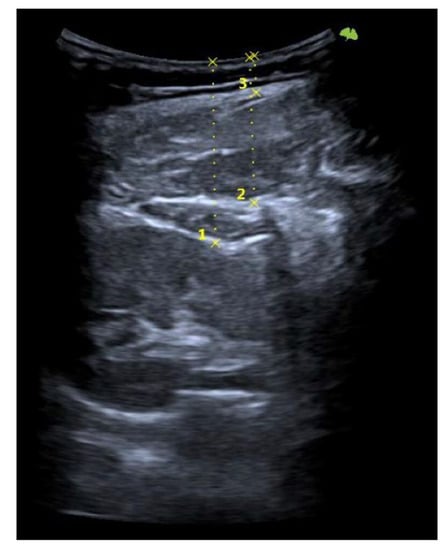

First, the last lumbar vertebra and the first sacral vertebra were located, and from there, the spinous processes of L4 and L2 were marked and assessed using ultrasonography. At the level of L2, the spinous process is located in the short axis, and the probe was moved to the right or left lateral side depending on randomization. We visualized the skin and the fatty tissue, we left the longissimus muscle towards the medial side, and we placed the iliocostalis lumborum muscle in the long axis, as well as the quadratus lumborum and the kidney, in the center of the screen. We asked the subjects to breathe in to see how the kidney descended and became more visible. When in maximum inspiration, we froze the image to make the following measurements: skin-upper edge of the iliocostalis lumborum muscle, skin-lower edge of the iliocostalis lumborum muscle, and skin-kidney. Then, a different researcher placed two fingers exerting pressure, as if it were the “tissue depression prior to performing the DP”. More ultrasound gel was placed between the fingers, and the sonographer placed the probe again in the short axis. An inspiration was requested to freeze the image and perform the same measurements mentioned above. At L4 level, the same protocol was followed with the difference in that, instead of performing the last skin-kidney measurement, the skin-peritoneum measurement was performed. The measurements were made on the right and left sides and with and without compression (Figure 3, Figure 4 and Figure 5).

Figure 4. Ultrasonography image. Short-axis view: skin (A), fat (B), thoracolumbar fascia (C), iliocostalis muscle (D), quadratus lumborum muscle (E), kidney (F), and peritoneum (G). Skin-kidney (1), skin-iliocostalis lumborum bottom edge (2), and skin-iliocostalis lumborum top edge (3).